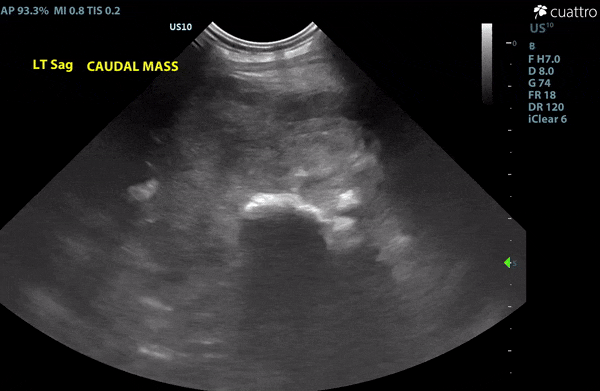

Image 1: Heterogenous mass distorting the margin of the rib and demonstrating signs of osteolysis and osteoproliferation.

Left thorax: There is a heterogeneous, mixed echogenic mass with punctate mineralization throughout, measuring at least 9.3 x 9.8 cm. The mass encompasses a left caudal rib from the lateral aspect of the rib extending into the pleural space. Within the mass, there are areas of disruption of the normal smooth contour of the rib margin, suggesting osteolysis. There is a moderate amount of mildly echogenic pleural effusion noted with suspended hyperechoic strands consistent with fibrin strands or pleural adhesions.